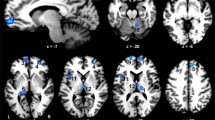

Localizer

Significant bilateral LOC clusters were identified in all but one participant. The average location of these clusters over all participants is shown in Fig. 2. For one participant, the specified contrast yielded no significant voxels with and without Bonferroni correction. Therefore, the average location of left and right LOC of all other participants was used in the MVPA analysis for this participant. The classification analysis was performed on both left and right LOC combined, as well as on separate left and right LOC voxels.